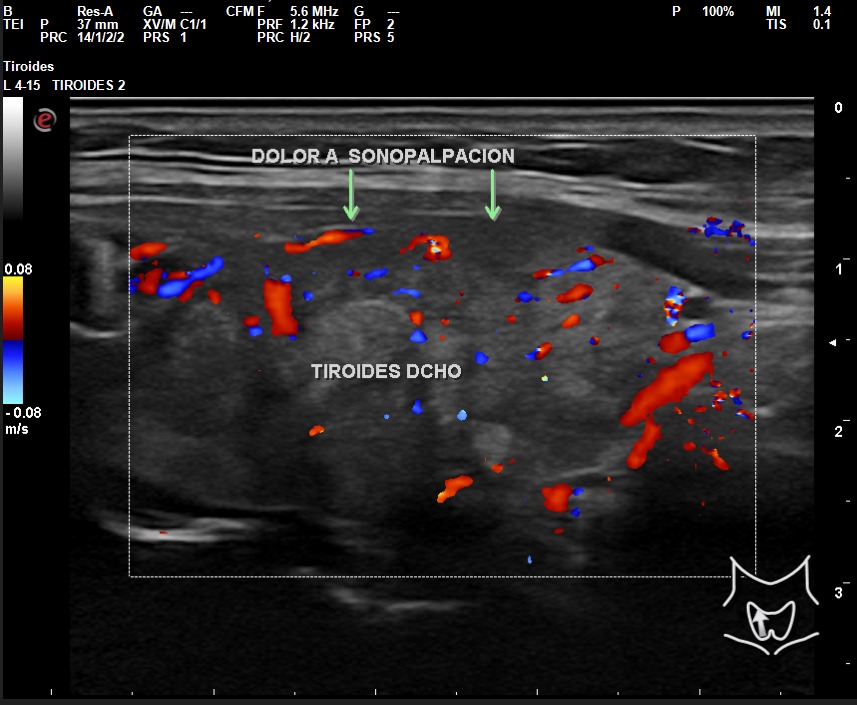

A la exploración ecográfica se observa en lóbulo tiroideo derecho áreas irregulares hipoecoicas sensibles a la sonopalpación con el transductor, con un ligero incremento de la actividad Doppler, asociado a la presencia de adenopatías de características reactivas y/o inflamatorias.

Los hallazgos ecográficos en otro contexto clínico, sin el dolor a la sonopalpación y sin el antecedente de posible viriasis previa, podrían ser muy parecidos al de un nódulo tiroideo sospechoso de malignidad: hipoecoico, márgenes irregulares, etc.